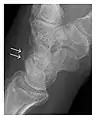

Triquetral fracture usually occurs on the dorsal aspect by impingement from the ulnar styloid or avulsion of strong ligamentous attachment. The dorsal avulsion fracture or "chip fracture" appears as a small bony fragment on the dorsal aspect of the triquetrum and is best detected on the lateral view(Figure 4). When radiography is negative in patients with high suspicion of a fracture, both MRI and MDCT will be of value. However, it has been shown that MRI is superior for detecting trabecular fractures in carpal bones.

a

b

Figure 4: Dorsal triquetral fracture of the left wrist in a 30-year-old man after a trauma. (a) Anteroposterior radiograph shows a normal appearance. (b) Lateral radiograph of the same wrist demonstrates a chip fracture off the dorsal aspect of the triquetrum (arrow).[1]